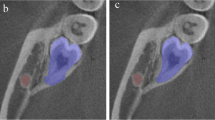

The buccolingual relationship of the M3 and the MC was determined by analysis of successive slices in multiplanar CBCT images by an oral and maxillofacial radiologist. The passing direction and path of the MC were evaluated based on the lamina dura of the M3. If the MC directly contacted or passed in close proximity to the inner surface of the M3 root, it was considered a lingual class, but if it directly contacted or passed in close proximity to the outer surface of the M3 root, it was classified as a buccal class (Fig. 1). We excluded the CBCT images in which it was difficult to determine the positional relationship between the MC and M3 for classification dataset. In our study, the radiologist annotating the images was unaware of critical information that could bias their assessments. This information included the patient's dental history, the patient's clinical symptoms, or demographic information. When the interpreter was not aware of the patient's clinical information, they were less likely to make assumptions about the patient's condition based on that information. This could lead to a more accurate interpretation of the image.

Examples of axial image (left), segmentation mask (middle), and SDM (right) of the mandibular third molar and the canal. The demarcation line was observed radially in the signed distance map, and the difference in direction was observed when the mandibular canals traveled along the lingual side or buccal side of the M3

The SDM was derived from the 3D SDT considering the internal shape of the object and the external relationship (Eq. 2), where B denoted the binary segmentation mask of the M3 and the MC. When calculating the SDM, the inside and outside of a boundary of an object had a negative and a positive value, respectively. In the SDM from the predicted M3 and MC segmentations, the values between the boundaries of the two objects formed a line that had a constant value. This information helped the networks to learn the geometrical relationship between the M3 and the MC.